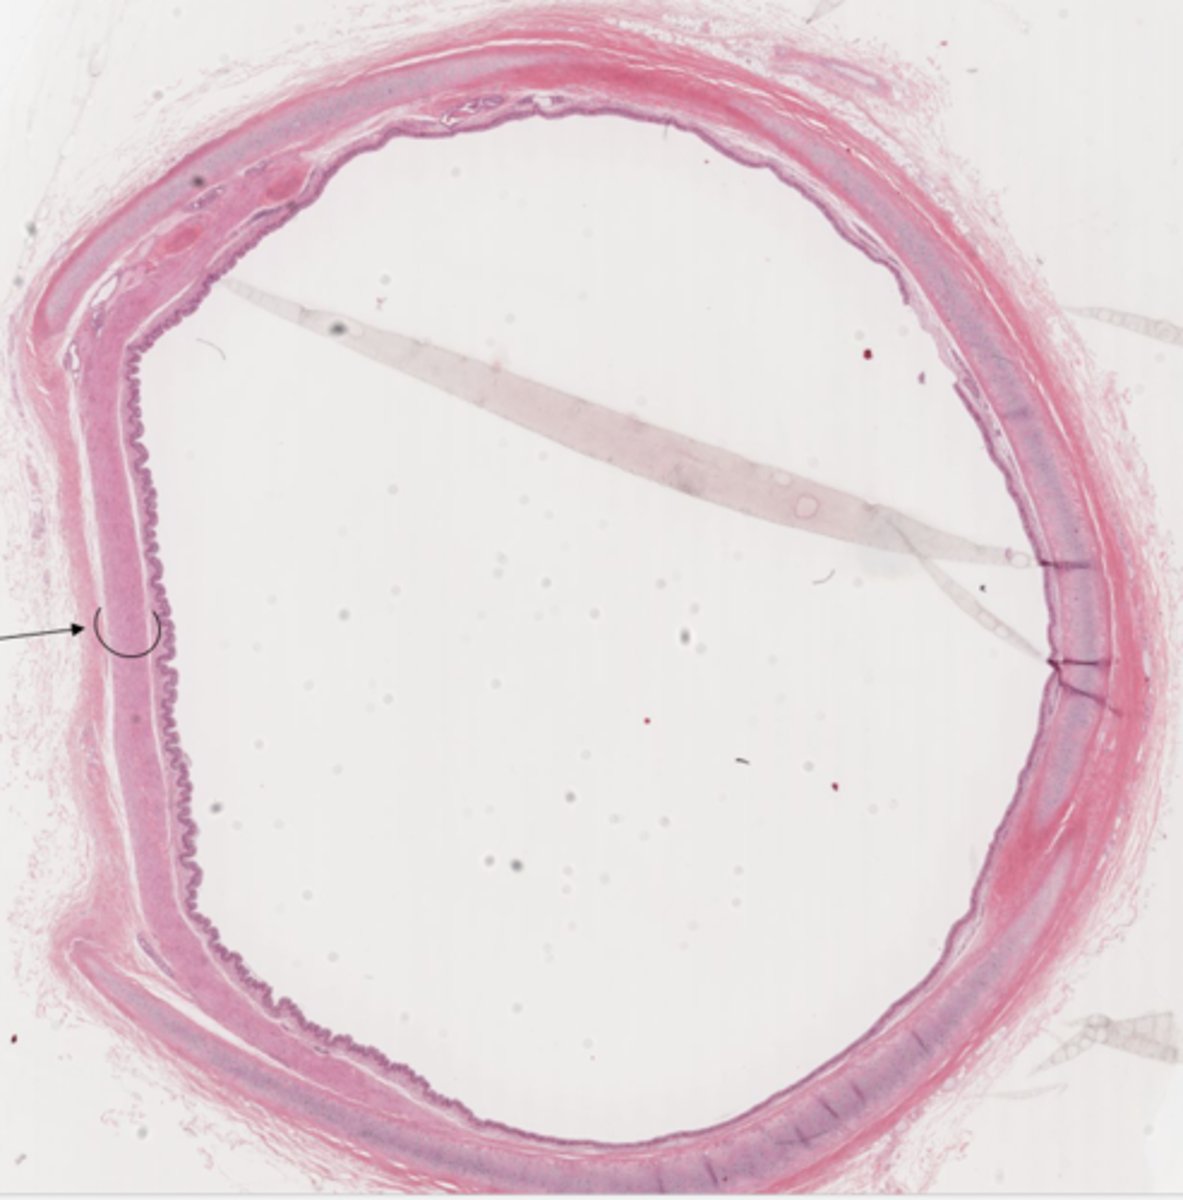

Identify the organ in cross section

trachea

Identify the organ

lungs

Classify the epithelium of the trachea

pseudostratified columnar ciliated with goblet cells

What is the name of this type of epithelium

respiratory epithelium

Identify the layer of the respiratory tract at 4

mucosa

Identify the layer of the respiratory tract at 2

lamina propria

These glands are in which layer of the trachea?

submucosa

Identify the gland in the mucosa and submucosa

seromucous gland

Identify the cell at 5

mucous cells

Identify the cell at 4

serous cells

Identify the muscle and organ

trachealis muscle of the trachea

Identify the structure in the trachea

secondary lymph node